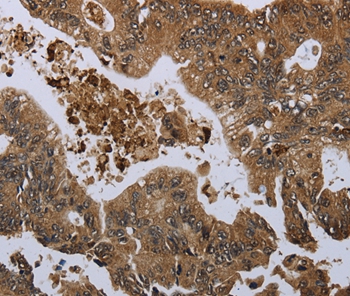

Immunohistochemical analysis of paraffin-embedded Human liver cancer tissue using #36512 at dilution 1/60.

Immunohistochemical analysis of paraffin-embedded Human colon cancer tissue using #36512 at dilution 1/60.